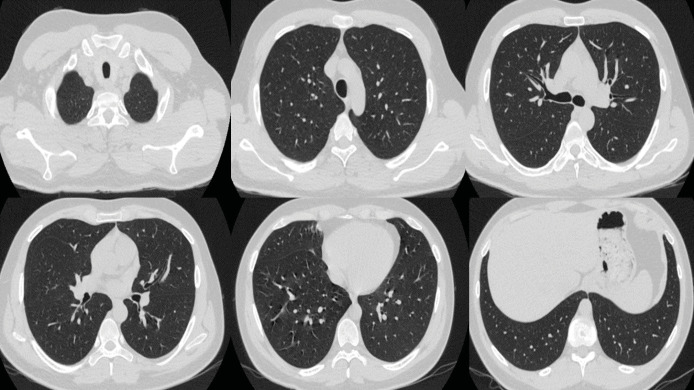

七氟醚是一种常用的吸入麻醉剂,用于诱导和维持全身麻醉。然而,它与一种罕见但严重的肺部疾病--弥漫性肺泡出血(DAH)--有关。弥漫性肺泡出血的特点是血红蛋白水平下降、弥漫性肺浸润以及伴有低氧血症的呼吸衰竭。我们介绍了一例在一次并不复杂的骨科手术中使用吸入七氟醚进行全身麻醉后出现 DAH 的健康年轻成人。值得注意的是,该患者没有其他风险因素或已知病因可能导致 DAH 的发生。

Sevoflurane is a commonly used inhalational anesthetic agent for inducing and maintaining general anesthesia. However, it has been associated with a rare but serious pulmonary condition known as diffuse alveolar hemorrhage (DAH). DAH is characterized by decreased hemoglobin levels, diffuse pulmonary infiltration, and respiratory failure with hypoxemia. We present a case of DAH in a healthy young adult who experienced this condition following general anesthesia with inhaled sevoflurane during an uncomplicated orthopedic procedure. Notably, there were no other risk factors or known causes that could account for the development of DAH in this patient.